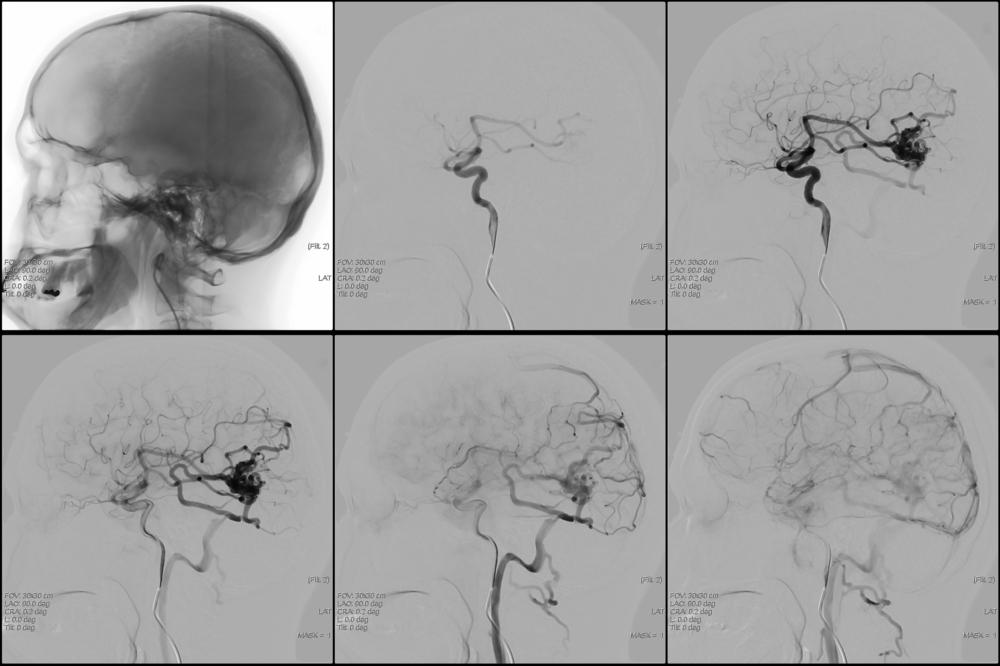

Для диагностики и выбора стратегии лечения могут быть рекомендованы следующие инструментальные методы исследования:

- МРТ (с контрастным веществом);

- КТ (как с контрастом, так и без);

- ангиография.